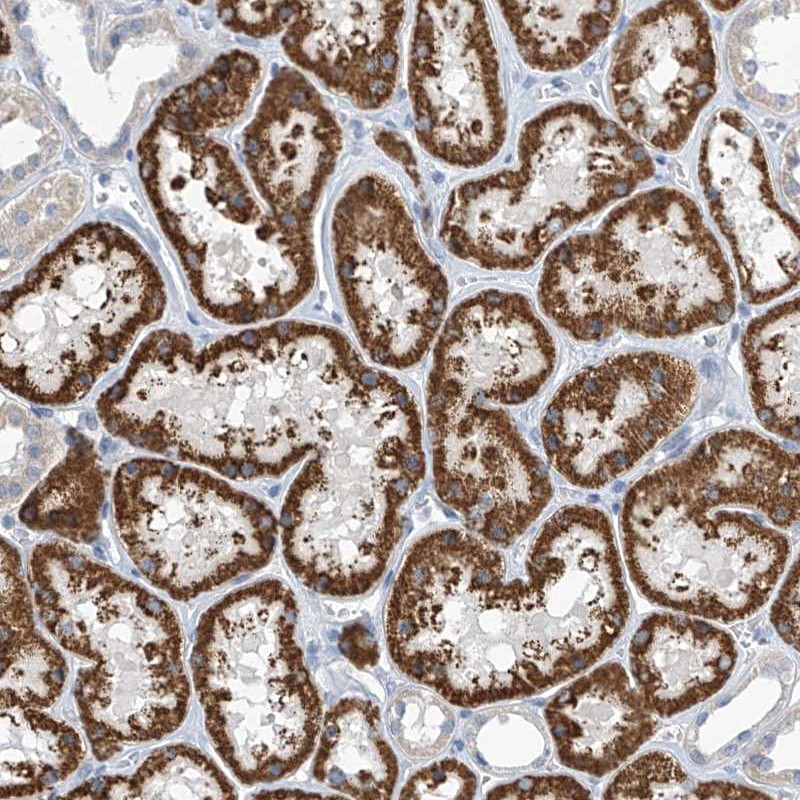

Immunohistochemical staining of human kidney shows strong cytoplasmic positivity in renal tubules.